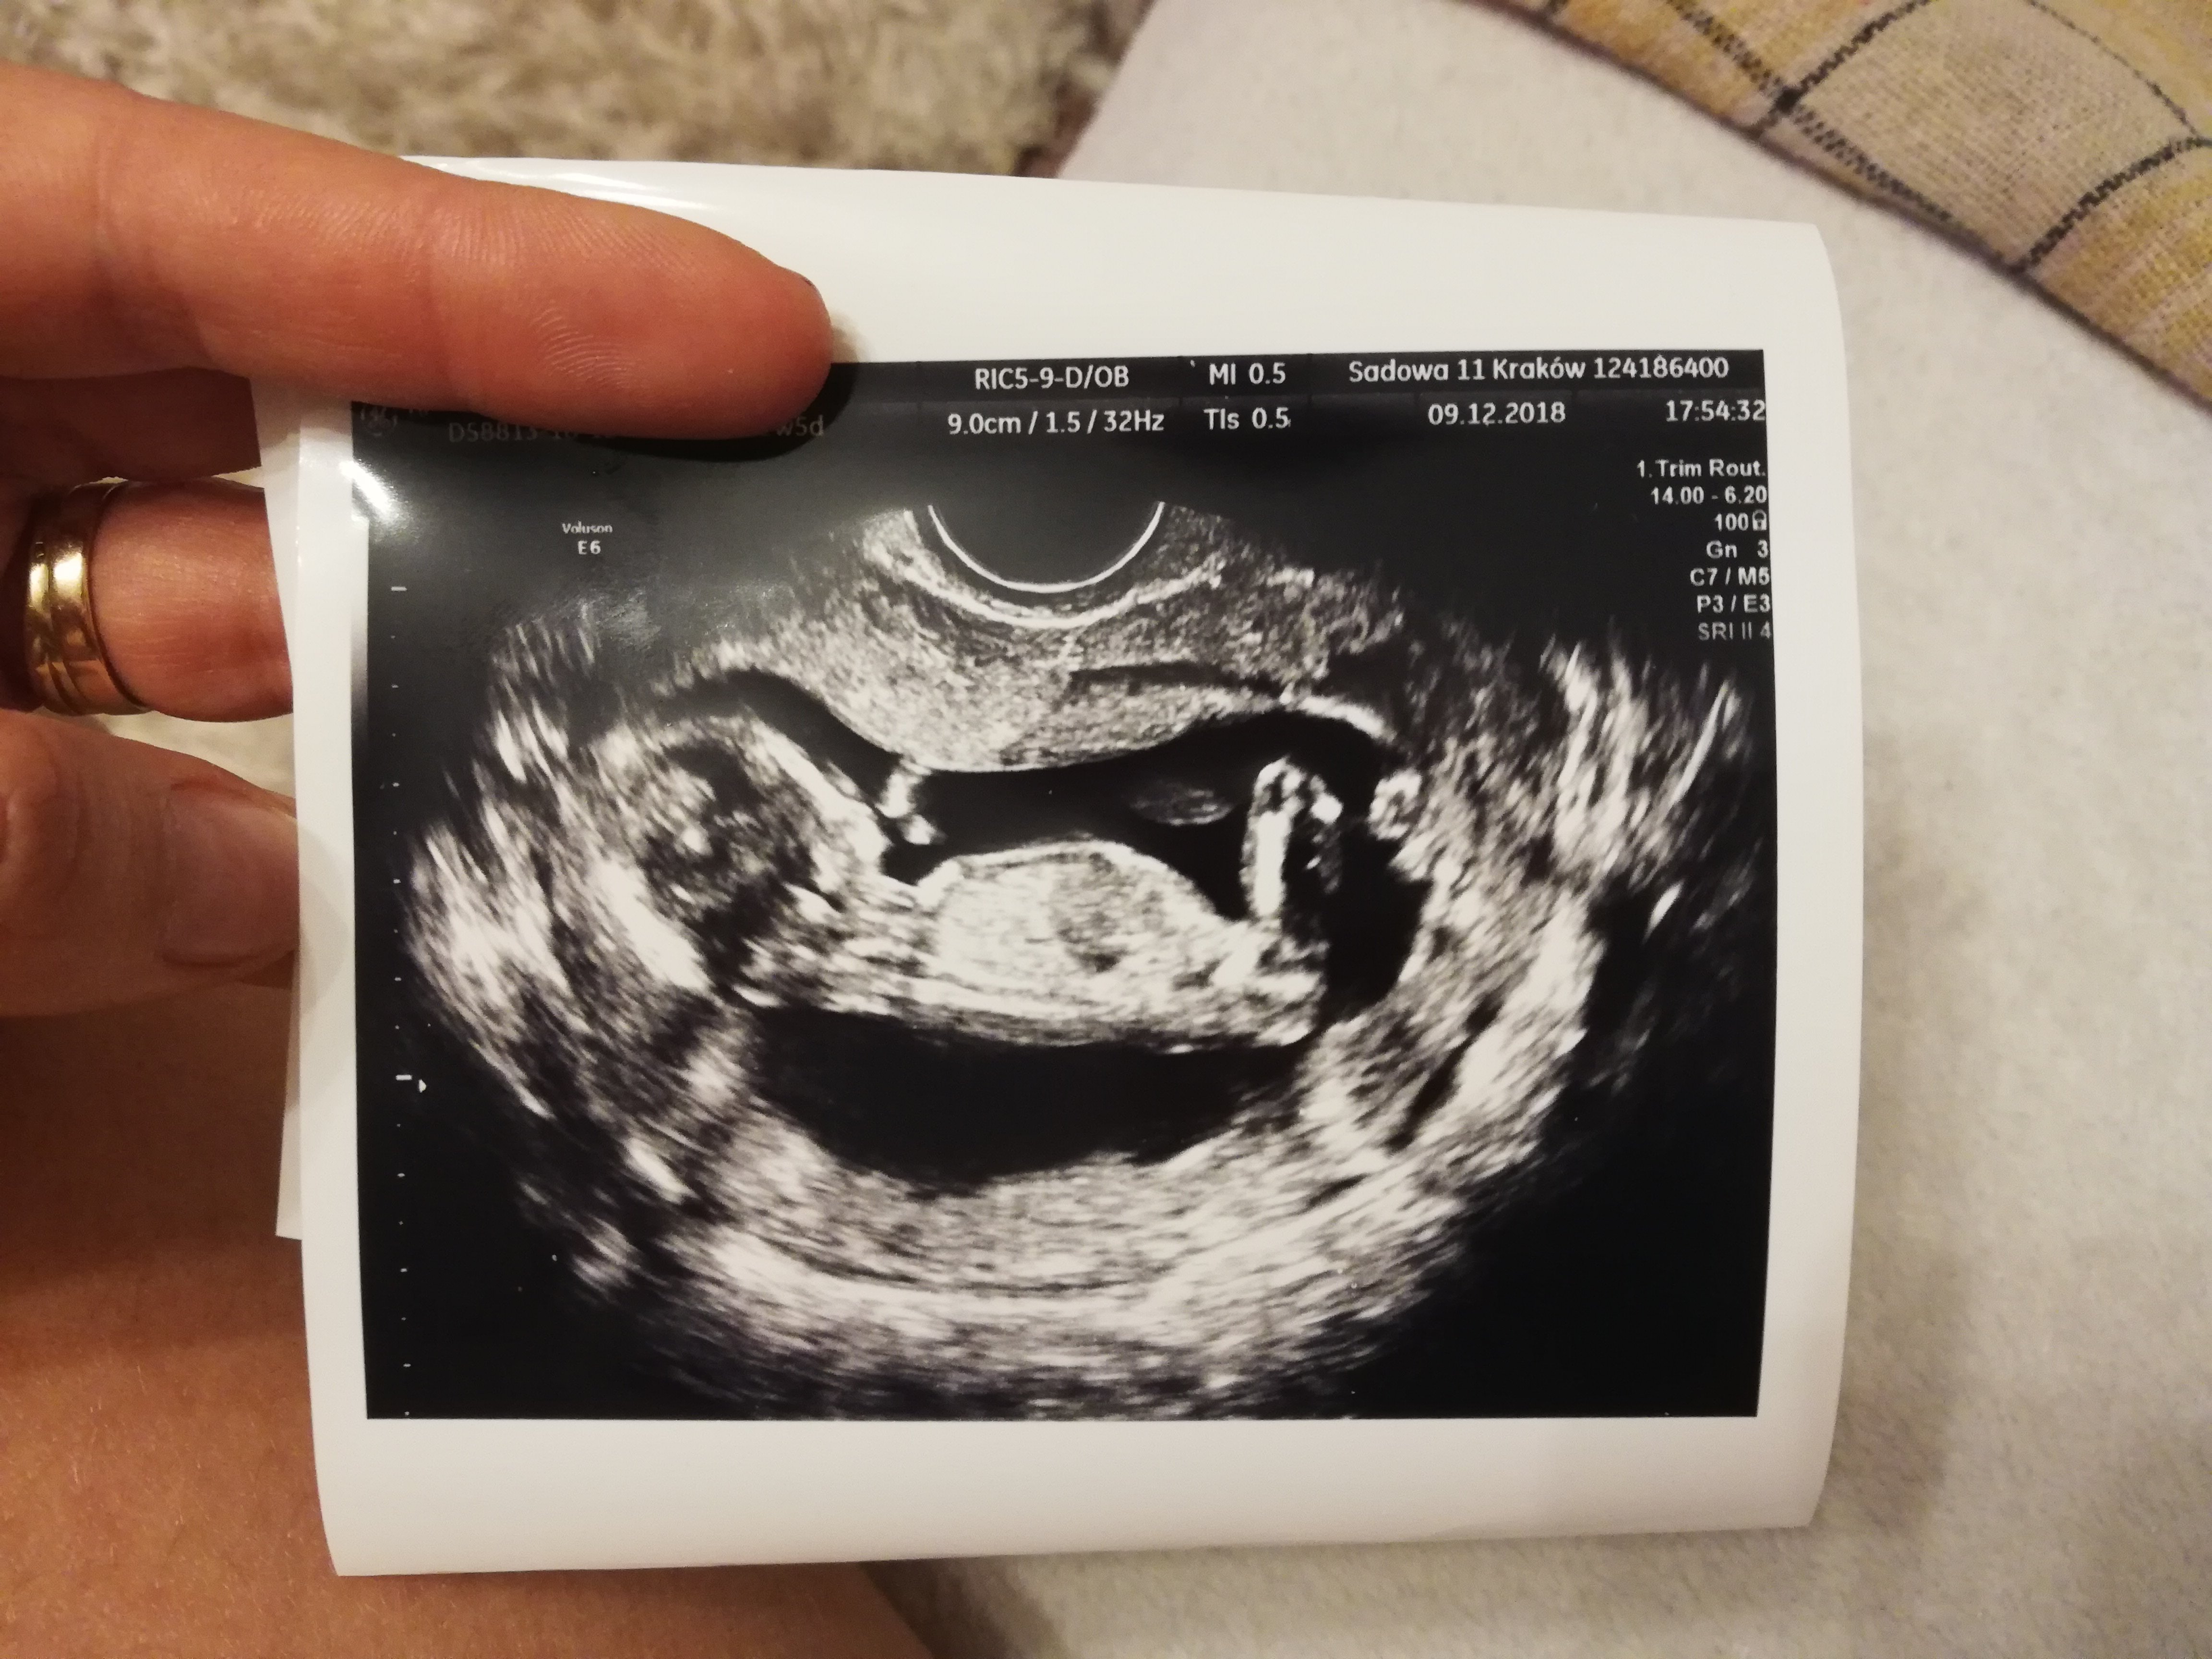

Dzisiaj mieliśmy wszystkie badania. NT 1,5 i kość nosowa obecna. Zrobiłam też dzisiaj test Pappa. Według usg mam 13+5 tc. Dzieciaczek ma 7,5 cm a z nogami 10 cm :)

Płci nie znamy, bo dziecię nie chciało pokazać. Następna wizyta 29 grudnia. Co do brzuszków to ja nie mam się czym chwalić bo w dalszym ciągu nic nie mam. W ciagu dnia jak dużo piję to brzuch się trochę powiększa, a tak to chyba znowu będę ciążę na placach nosić jak poprzednia..

A tu bobas :)

A tu bobas :) Zobacz załącznik 923552